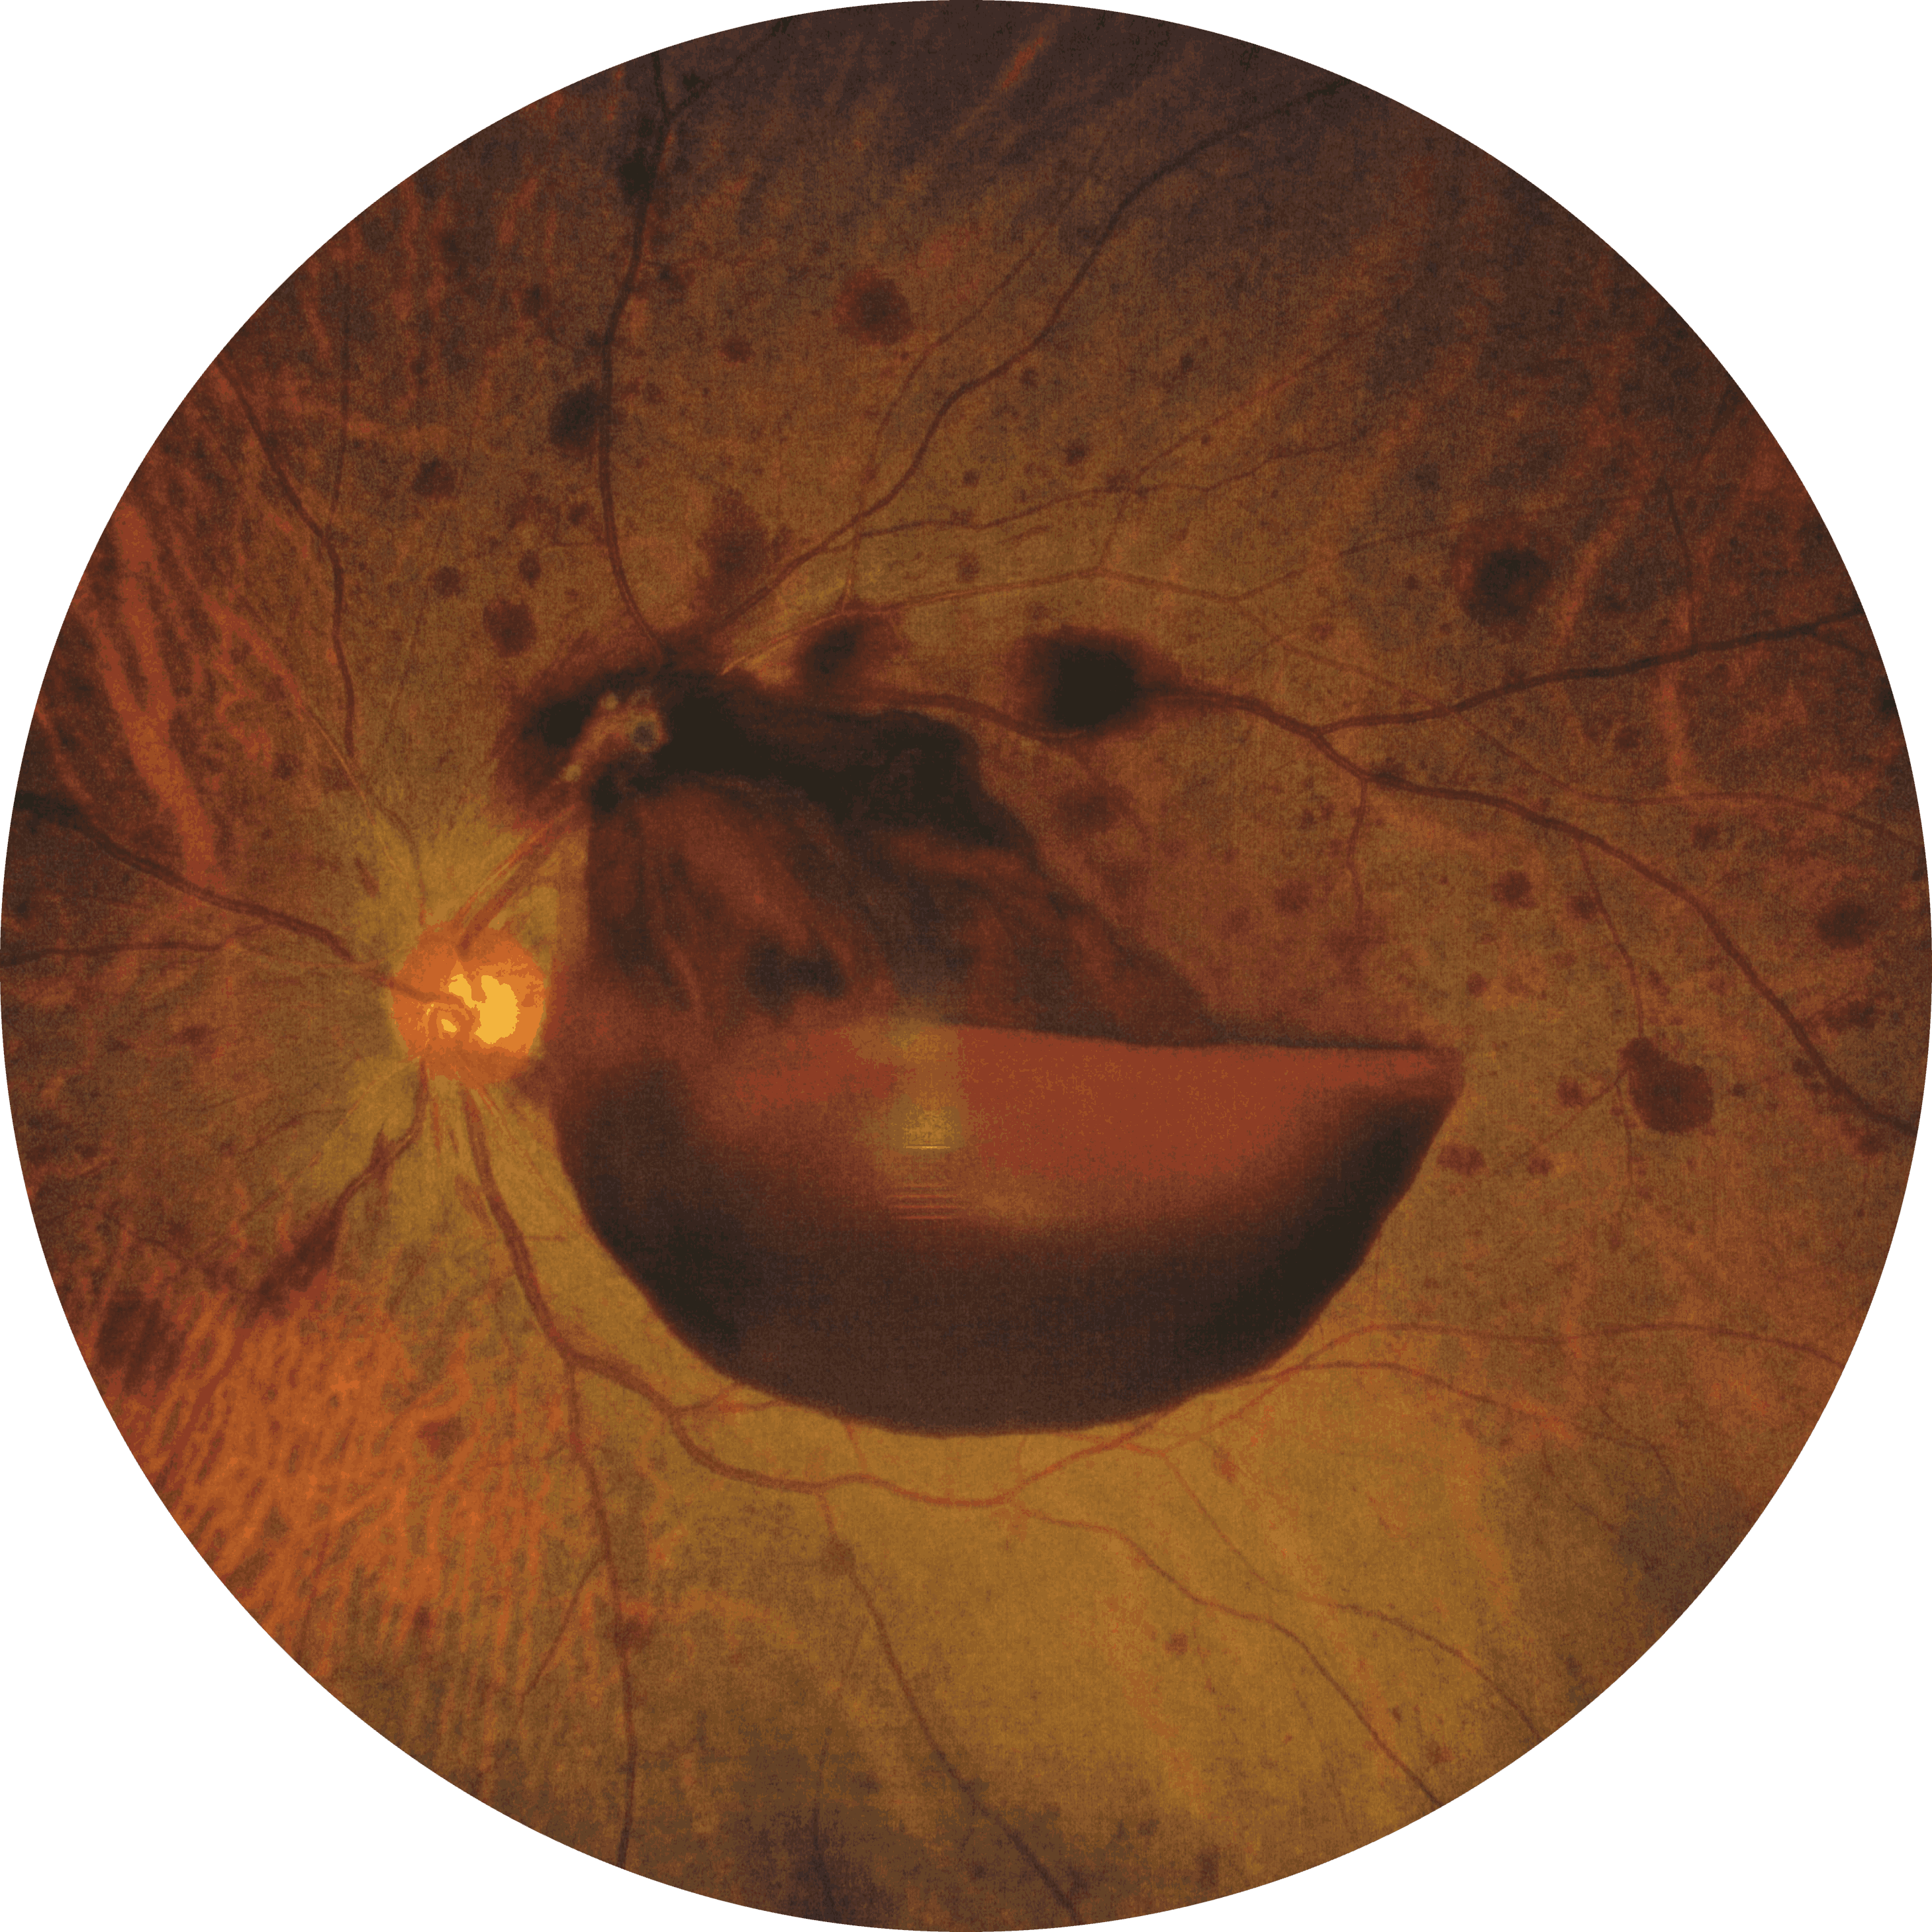

RETINAL TORNADO: THE FURY OF GIANT RETINAL TEAR. Optos ultrawield field retinal imaging camera image

Author: Dr. ABHISHEK G NAIR

View